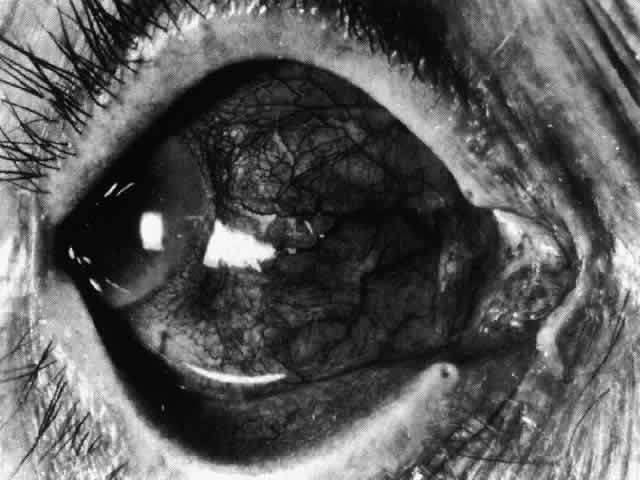

In this relatively benign form of scleral inflammation, the fluorescein

angiogram reveals a rapid flow pattern in which the transit time of the

dye is very rapid (as in episcleritis) (Figs. 32 and 33). Subtle changes occur in the capillary network, and abnormal leaking

vessels appear after prolonged inflammation. These changes do not disappear

after the inflammation subsides or is treated (see Fig. 31).  Fig. 32. Diffuse anterior scleritis associated with corneal edema. The limbal vessels

Fig. 33. Fluorescein angiogram of patient in Figure 32 four seconds after the appearance of the dye. This is a very rapid transit

time. All the limbal capillaries are completely full, and all the

major episcleral vessels contain fluorescein. Note that the very large

vessel is a vein, and the narrow vessel below it is an artery. The deep

vessels are distorted, and some are abnormal in configuration. Fig. 33. Fluorescein angiogram of patient in Figure 32 four seconds after the appearance of the dye. This is a very rapid transit

time. All the limbal capillaries are completely full, and all the

major episcleral vessels contain fluorescein. Note that the very large

vessel is a vein, and the narrow vessel below it is an artery. The deep

vessels are distorted, and some are abnormal in configuration.

|